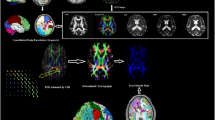

Figure 11 shows the averaged density map of tracts originating from the gyrus rectus, insular cortex, precuneus and superior temporal gyrus, for the cohorts of left and right mTLE patients. As can be seen, fewer tracts were reconstructed originating from the ipsilateral insular cortex (posteriorly) and superior temporal gyrus, compared to the side contralateral to the epileptogenicity. A substantial interhemispheric variation of the density map was also observed for the gyrus rectus only in the left mTLE cohort.

Averaged density map of tracts overlaid upon the MNI registered brain (Xia et al. 2013), between the gyrus rectus (a), insular cortex (b), precuneus (c) and the superior temporal gyrus (d) as the input ROI and all other anatomical ROIs. The density maps are averaged on the left mTLE patients (left images) as well as right mTLE patients (right images). Note that in (b), the tracts originating from the insular cortex are deep intracranial tracts and cannot be rendered on the surface of the MNI registered brain (Color figure online)